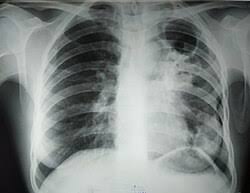

Pnewmoniýa

26

0